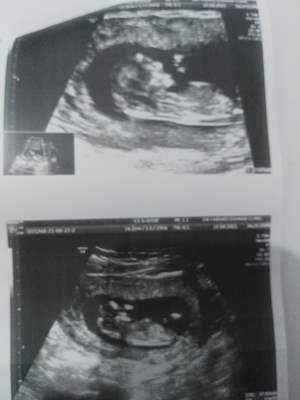

سلام خوشگلا امروز رفتم ان تی..بنظرتون جنسیت نی نی چیه عکس الان میفرستم براتون باتجربه ها بگن مرررسی